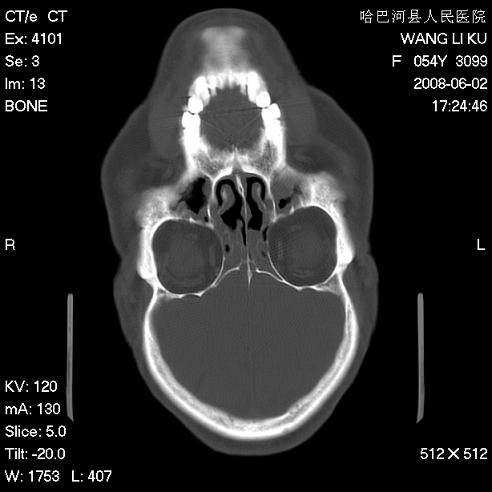

标题: CT13803:反复性鼻塞、流涕一年余 [打印本页]

标题: CT13803:反复性鼻塞、流涕一年余

副鼻窦炎,右上额窦积脓。左眼肌锥内见致密影,视神經受压

1.全组副鼻窦炎2.双侧上颌窦积液

全组副鼻窦炎 肌锥内高密度灶。建议进一步检察检查

1、全组副鼻窦炎。

2、左眼眶肌锥内病变,小血管瘤?建议增强。

1)全副鼻窦炎(左侧上颌窦黏膜下囊肿或息肉)。2)左眼眶肌锥内不规则小结节状软组织密度影;考虑为小血管瘤可能。建议行ct增强扫描检查。

全组副鼻窦炎,左侧肌锥内不规则形软组织肿块影,与眼外肌密度相当,左侧视神经受压,肿块与视神经及眼外肌分界清晰,眼外肌无增粗,眶壁无破坏,球后脂肪间隙不模糊,考虑良性改变,小血管瘤或神经源性肿瘤可能,建议增强扫描。

谢谢,增强扫描做了,眶内病灶与海绵窦同步明显强化,血管瘤